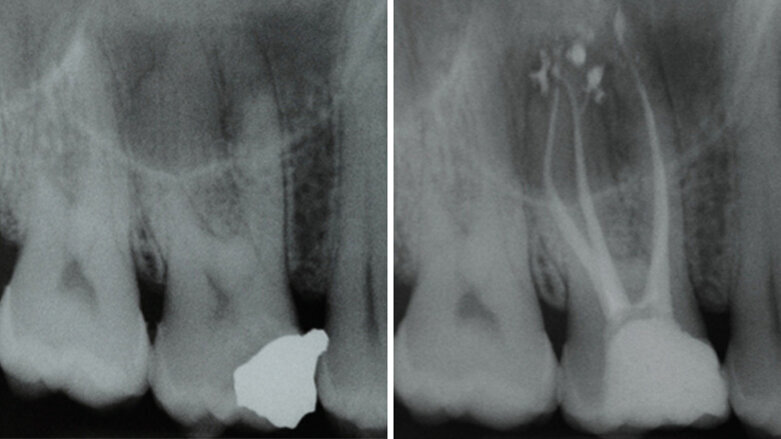

In vitro a ex vivo studie ukázaly přítomnost bakterií v dentinových tubulech a cementu i po endodontickém ošetření, což zdůrazňuje, že cíl absolutní dezinfekce kanálku není pravděpodobně dosažitelný pouhým čištěním a opracováním.Plnění opracovaného kořenového kanálku je následným krokem v endodontické terapii a slouží jako prevence bakteriální reinfekce zubu a periapexu. Většina obturačních systémů v endodontické terapii je složena ze základního materiálu a sealeru. Sealer by měl nejen vyplnit mezery mezi základním materiálem a stěnou kořenového kanálku, ale také povrchové nerovnosti systému kořenových kanálků (jako jsou laterální kanálky a isthmy), aby bylo dosaženo pevného utěsnění (obr. 2a, b).K překonání problému bakteriální persistence v systému kořenových kanálků byly postupně vyvíjeny a uváděny na trh materiály s antibakteriálními vlastnostmi. Antibakteriální povaha sealeru je cenná kvůli vyššímu procentu fakultativních anaerobů v případech selhání léčby kořenových kanálků. Objevilo se několik sealerů na bázi pryskyřic a MTA, u kterých výrobci tvrdili, že mají schopnost zničit bakterie ponechané v dentinu kořenových kanálků, avšak literatura ukázala, že antimikrobiální sealery (především sealery na bázi pryskyřice) jsou efektivnější, když jsou čerstvě namíchány, a jejich aktivita se snižuje po ztuhnutí,a tedy se na ně nelze spoléhat v prevenci reinfekce v průběhu delšího období.

Úspěšná terapie je, když jsou plnicí materiály schopny pevně utěsnit prostor kořenových kanálků, a to i v případě více výstupů